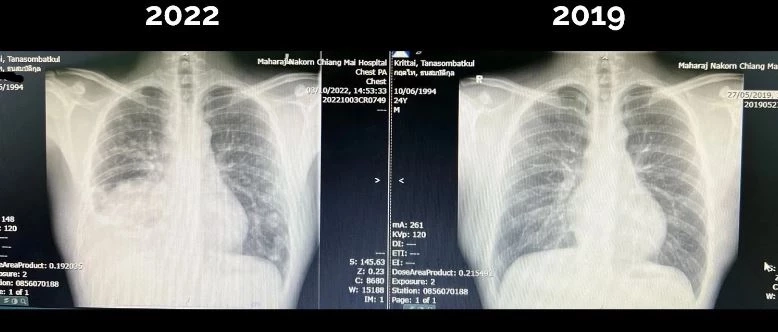

แล้วคุณหมอก็เริ่มมีอาการไอ ไอมีเสมหะบ้าง ไอแห้งบ้าง จนกระทั่ง เข้าตรวจก็พบว่า เป็น "มะเร็งปอด" ระยะสุดท้าย ตัวก้อนหลักขนาดเกือบ 8 ซม. ที่ปอดด้านขวา นอกจากนี้ ตัวมะเร็งยังมีการกระจายไปที่เยื่อหุ้มปอด และปอดข้างซ้ายอีกหลายจุด ที่สำคัญคือ มันกระจายไปที่สมองถึง 6 ก้อนด้วยกัน

ปลายเดือน พ.ย.65 คุณหมอกฤตไท โพสต์ผ่านเพจฯ ระบุ มีแรงมากขึ้น เริ่มวิ่งได้แล้ว ส่วนอาการป่วย เอกซเรย์ปอดดูดีขึ้น ก้อนใหญ่ด้านขวามีขนาดเล็กลง และก้อนน้อยๆ ที่ปอดซ้ายก็ดูจางลง